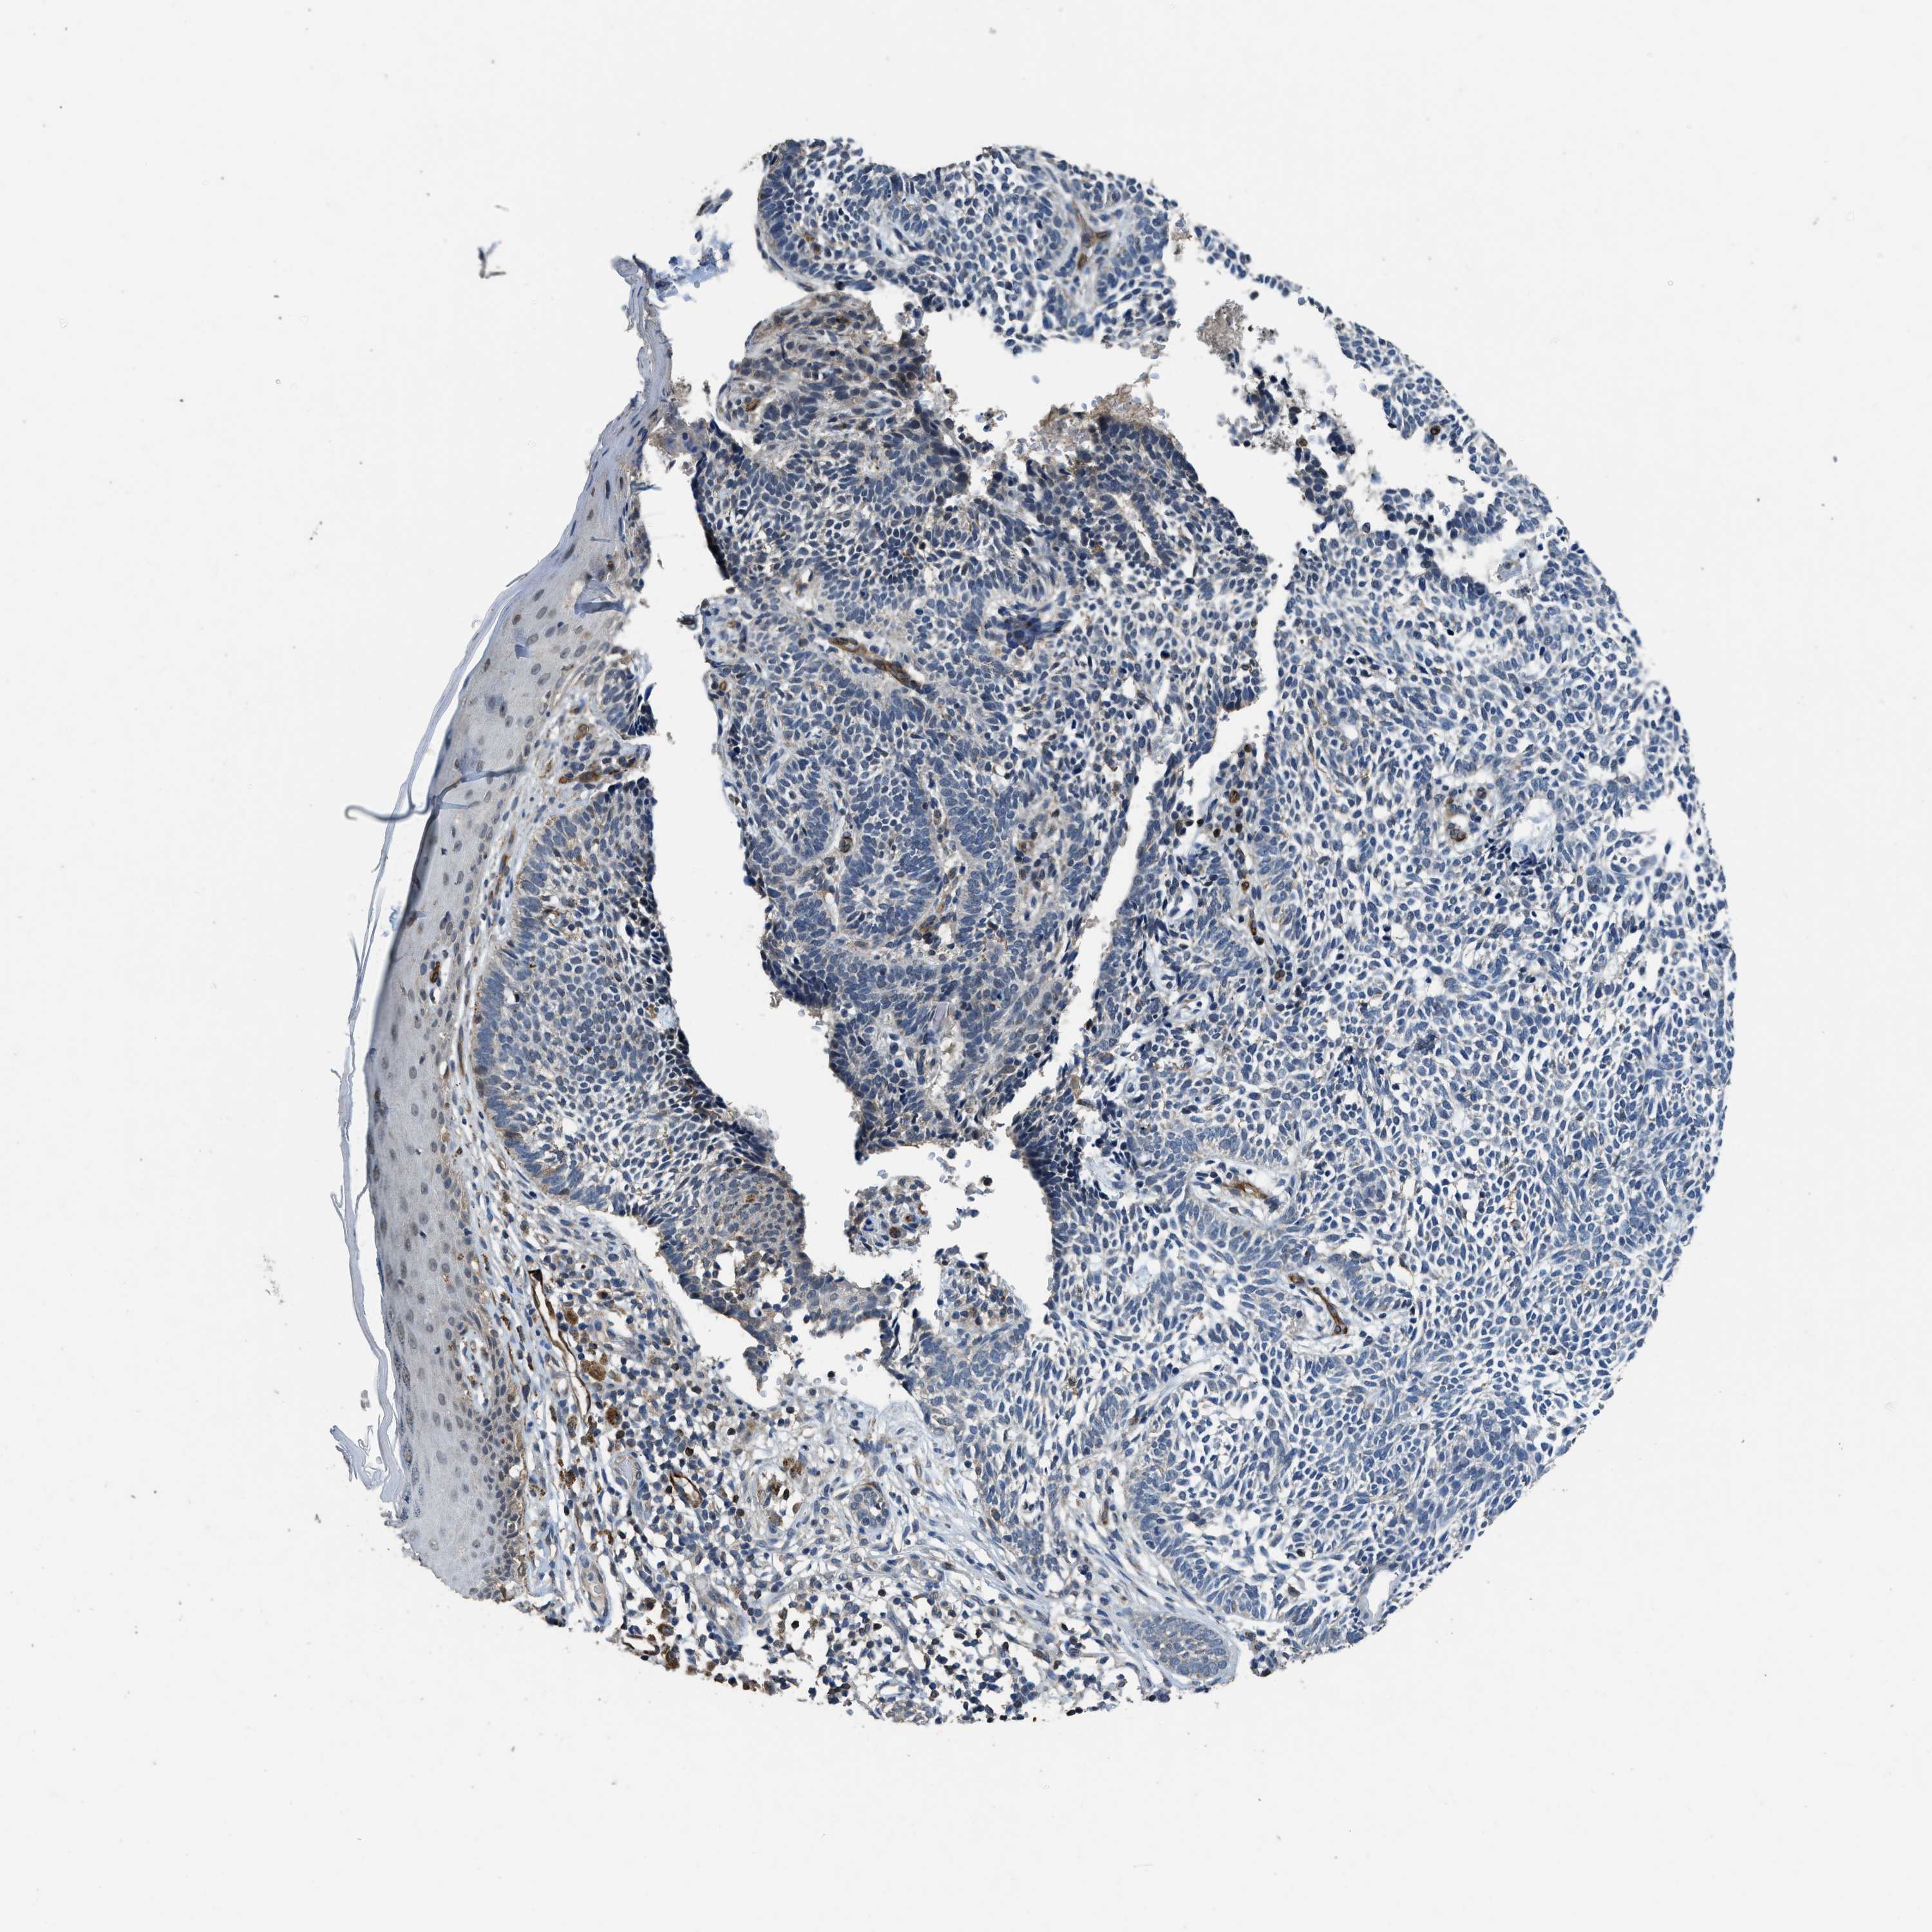

CANCER SKIN CANCER Show tissue menu

Basal cell and squamous cell cancer

SKIN CANCER - Protein expressioni

A mouse-over function shows sample information and annotation data. Click on an image to view it in a full screen mode. Samples can be filtered based on level of antibody staining by selecting one or several of the following categories: high, medium, low and not detected. The assay and annotation is described here.

Each image is clickable and will lead to virtual microscopy that enables deeper exploration of all samples and also displays staining intensity scores, fraction scores and subcellular localization as well as patient and tissue information for each sample.

Antibody HPA044200

Squamous cell carcinoma, NOS